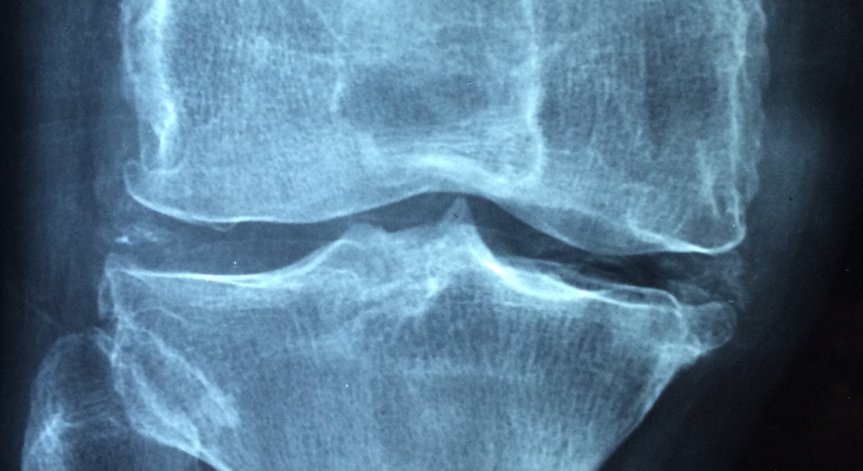

Ново проучване показва тревожна връзка между по-високите нива на замърсяване на въздуха и по-бързата загуба на костна маса в резултат на остеопороза - хронично състояние на скелета, което прави костите по-крехки и по-склонни към счупване, съобщи "Сайънс Алърт".

Рискът от остеопороза нараства с възрастта и е особено често срещан при жените в постменопауза. В продължение на 6 години са събирани данни за разнообразна група от 9041 жени в постменопауза, като изследователите са разглеждали по-специално костната минерална плътност: косвен показател за остеопорозата и риска от фрактури.

Използвайки домашните адреси за оценка на азотния оксид, азотния диоксид, серния диоксид и праховите частици PM10 (замърсяване, по-малко от 10 микрометра - диаметърът на червената кръвна клетка), изследователите установяват, че с увеличаване на замърсяването -костната минерална плътност намалява във всички области на костите в тялото, включително шията, гръбначния стълб и бедрото.

Прада и колегите му подчертават връзката между азота и гръбначния стълб. Скокът с 10% на този вид замърсяване за 3 години е свързан със средна годишна загуба от 1,22% в костната минерална плътност на лумбалния отдел на гръбначния стълб, което е два пъти повече от количеството, изчислено от екипа при нормално стареене. Според изследователите това най-вероятно се дължи на смъртта на костните клетки, причинена чрез механизми, включващи оксидативен стрес, при който токсичните молекули от околната среда нанасят щети на организма.